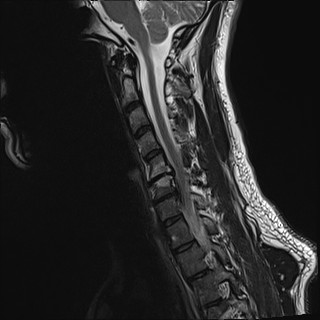

Wirbelsäule HWS

t2_tse_sag